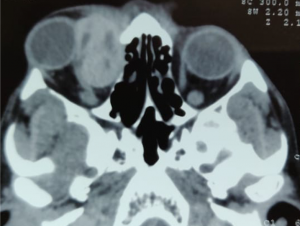

CT- lobulated soft tissue msses, opacification of paranasal sinuses with high attenuation content with enhancing adjacent orbital soft tissue

| Invasive Sino-orbital fungal disease[15] | Immunocompromised (mucormycosis)

Imuunocompetent (aspergillosis) |

Severe limitation of EOM with associated chemosis and blepharoptosis.

In mucormysosis, very acute progression of disease with presence of black nasal fliuid, eschar or skin discoloration (characteristic). On fundus examination, CRAO present. In aspergillosis, sub acute progression. |